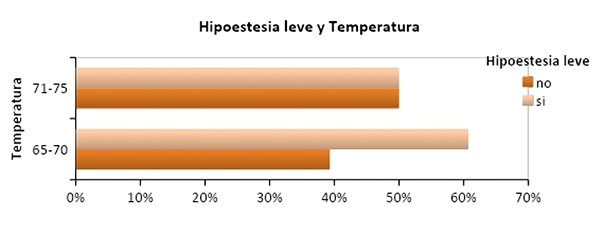

En el análisis de los pacientes que fueron operados por primera vez con respecto a las complicaciones posteriores se observó que, permanecieron con hipoestesia leve 17 (60%) pacientes en el grupo de 65°C-70°C y 15 (50%) pacientes en el grupo de 71°C-75°C sin significación estadística (p=0,41) (graf. 8), cuando se analizó la variable hipoestesia mayor (molesta) entre los pacientes operados por primera vez se objetivó que la sufrieron 1(3%) paciente para cada grupo de temperaturas, sin significación estadística (p=1,00) (graf. 9).

Gráfico 8: Relación entre hipoestesia leve y grupo de temperatura (p=0,42).

Se observó que, permanecieron con hipoestesia leve 17 (60%) pacientes en el grupo de 65°C-70°C y 15 (50%) pacientes en el grupo de 71°C-75°C similar a lo que se observó en otras series.8,13